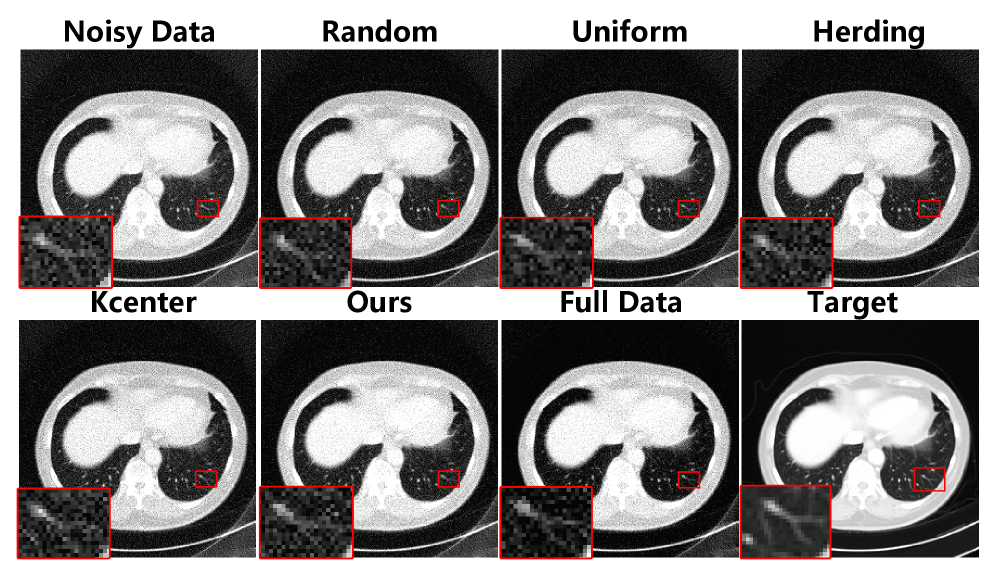

Image Restoration Tasks. To verify that our method is not only applicable to the super-resolution task, we test it on the CT restoration task. Specifically, we employ the classical REDCNN [26] for LDCT restoration. As shown in Tab. 3, our method achieves the best restoration performance, comparable to training with the full dataset. Additionally, we present our quantitative results in Fig. 5. It can be observed that the denoised results obtained using our distilled dataset exhibit higher image quality and better preservation of fine details.

Refer to caption

Figure 5: Qualitative results of different algorithms.